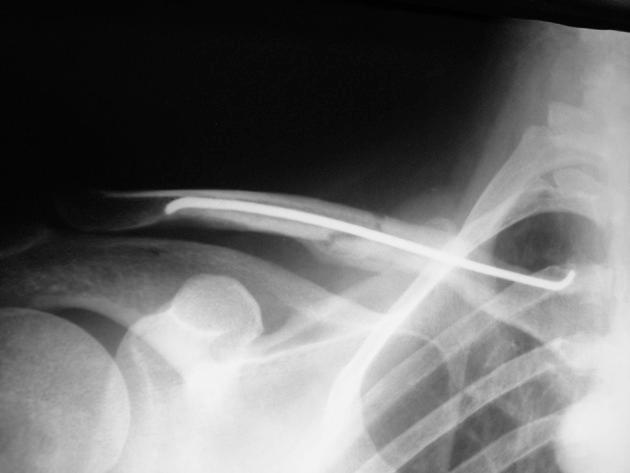

One of the modern techniques for the treatment of clavicle fracture (Fx) is elastic titanium intramedullary nailing. But, there are different opinions about this technique. We studied this technique in 12 patients with clavicle Fx and assessed its outcome.

We operated on 13 clavicle Fx in 12 patients from 2008 through 2012. We used a new technique called minimally invasive titanium elastic intramedullary nailing for operating patients with midshaft clavicular Fx.

Clinical union was achieved 3-5 weeks after the operation with no pain over Fx sites upon physical examination. Radiologic union appeared at 6 to 12 weeks .We did not encounter nonunion or infection, but one of the comminuted Fx united 1 cm shorter; however, it had a solid union with a good score. All but two patients had good scores.

Although controversy exist regarding intramedullary nailing of clavicle Fx, our results using this technique for minimally comminuted midshaft clavicular Fx were very good.